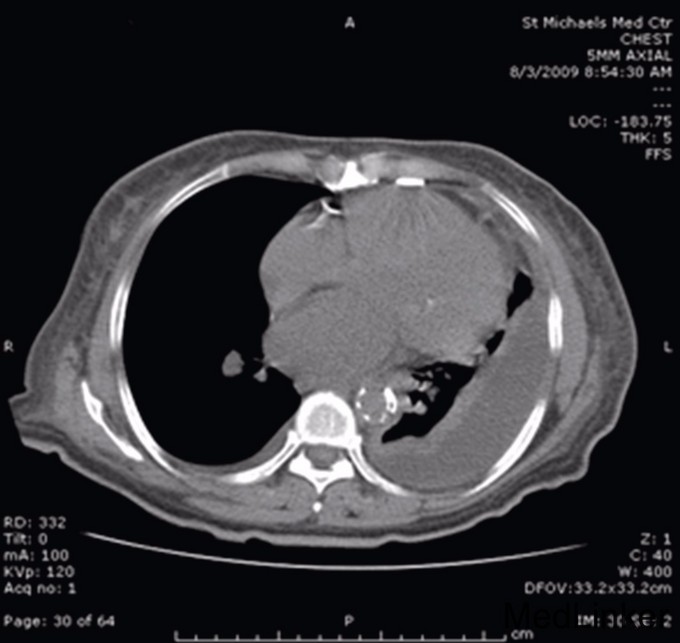

查体:左肺底部闻及浊音,呼吸音降低,未闻及干湿啰音。下肢有水肿, 无杵状指,未查见特殊。血常规提示血象高,白细胞11800/mm3,中性粒细胞占84%,淋巴细胞占9%。胸部X线显示左胸下三分之二混浊(图1),胸部CT提示左侧胸部大面积包裹性积液(图2),胸水生化常规提示乳酸脱氢酶292U/L,总蛋白4.0 g/dL,白细胞1033/mm3,革兰染色球杆菌阳性。根据light标准判断胸水为渗出液。